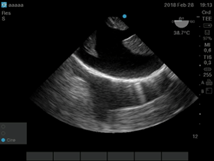

Ante un evento agudo de taponamiento cardíaco, intubado el paciente, se coloca ETE para valorar la situación hemodinámica y guiar la punción y el drenaje. (Figura g)

Figura g: Imágenes transgástricas a 0 grado donde se ve taponamiento cardíaco con compresión del ventrículo derecho(VD) y luego del drenaje expansión del VD